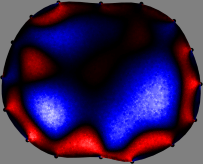

Figs. 3 and 4 compare the performance of the proposed FER method in (20) with the standard regularized least-squares method ((19) when \mathcal{R} is the identity matrix). The regularization parameter of the standard method was heuristically chosen for its best performance, and the parameter of the FER method was set to be one of three different values λ=0.05,0.2,𝜆0.050.2\lambda=0.05,0.2,\infty. The injection current was 1 mARMSRMS{}_{\tiny{\mbox{RMS}}} at 100 kHz, and the frame rate was 9 frames per second. The reference frame at t0subscript𝑡0t_{0} was obtained from the maximum expiration state. The measured data, 𝐕˙(tm)˙𝐕subscript𝑡𝑚\dot{\mathbf{V}}(t_{m}), represent the voltage differences between each time tmsubscript𝑡𝑚t_{m} and t0subscript𝑡0t_{0}. The blue regions, which denote where conductivity decreased by inhaled air, increased during inspiration and decreased during expiration. The FER method with λ=𝜆\lambda=\infty was clearly more robust than the standard method that produced more artifacts originated from the inversion process.

Figure 3: The reconstructed images of the conductivity change of the subject A by the standard regularized least square method and the proposed fidelity-embedded regularization (FER) method for three difference values λ=0.05,0.2,𝜆0.050.2\lambda=0.05,0.2,\infty. Here, the time step is 0.22 seconds (tm+2tm0.22subscript𝑡𝑚2subscript𝑡𝑚0.22t_{m+2}-t_{m}\approx 0.22).